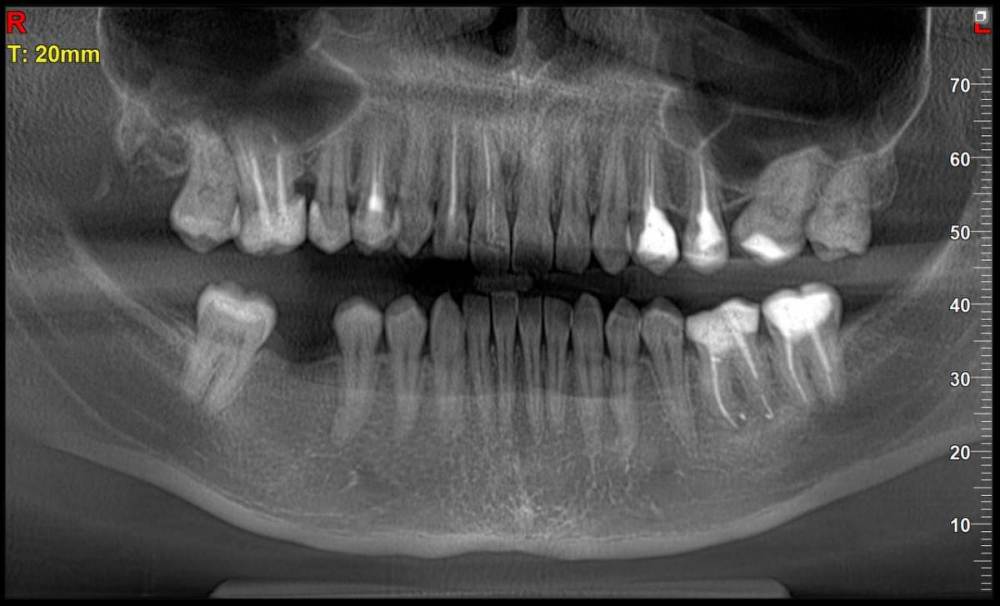

Сейчас я обратилась к ортодонтам с целью выровнять только нижний зубной ряд (искривлен из за воздействия 8ок), с последующей установкой импланта (46 зуб). Нижние восьмерки удалены.

26 отсутствует, 27 стоит на месте 26, 28 стоит на месте 27

11 сломан в корне, держится на штифте + пломба соединяющая его с соседними зубами.

Есть ли воспаления? (если это можно определить по моему панорамному снимку).

15-16 зуб - черная дыра - что это может быть? Есть ли шансы спасти?